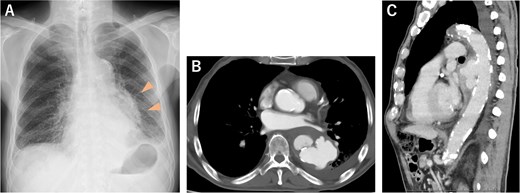

An 81-year-old male patient was transferred to our institution with chest radiographic abnormalities and an increased inflammatory response. The patient had a fever 2 weeks before admission, was diagnosed with a urinary tract infection (UTI), and was treated with oral levofloxacin (LVFX) by the patient’s doctor. The fever reduced following the administration of LVFX; however, follow-up chest radiography revealed an abnormal shadow in the left lung field (Fig. 1A). On admission, the physical examination results were normal: afebrile, no haemodynamic instability, and no specific symptoms. Contrast-enhanced computed tomography (CECT) revealed a thoracic aortic rupture (Fig. 1B and C). Therefore, the patient underwent emergency thoracic endovascular aortic repair (TEVAR) with a Zenith Alpha (32 × 155 mm; W. L. Gore & Associates, Flagstaff, AZ). The operation was successfully performed with no obvious complications (Fig. 2).

(A) Chest radiograph 3 days before admission showed an abnormal shadow in the left lung field (arrowheads). (B, C) CECT on admission revealed a descending thoracic aortic rupture.